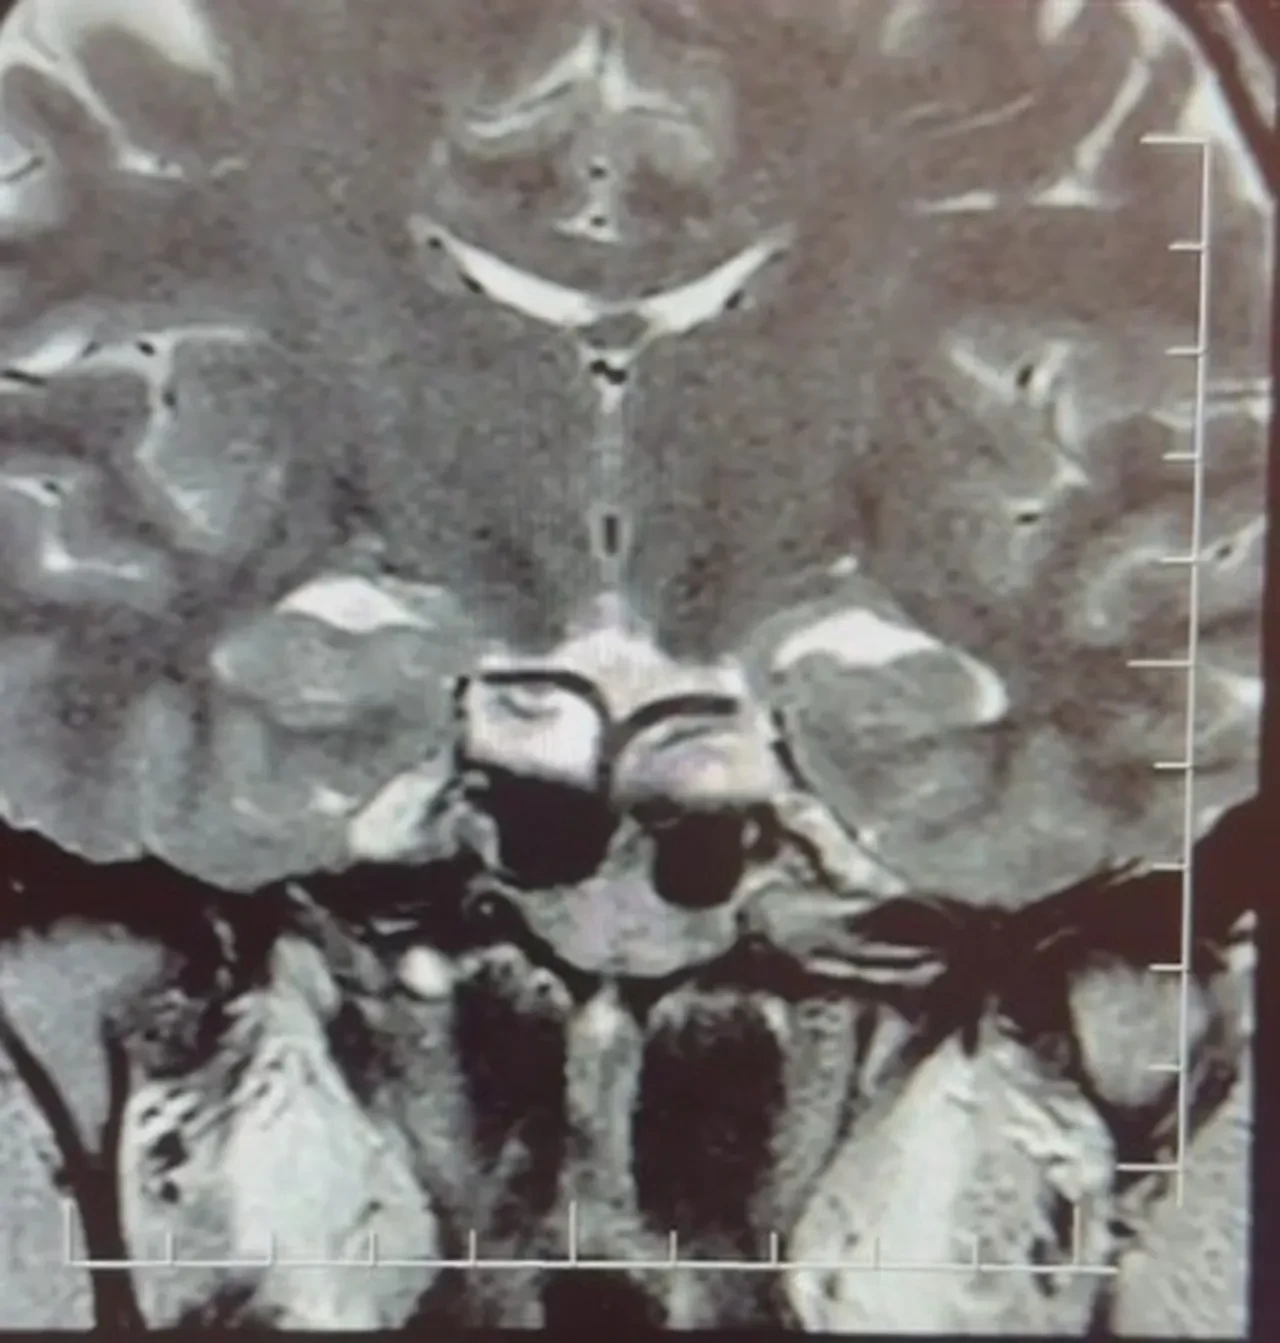

Yapılan ileri tetkiklerde hastaya hipofiz MR çekildiğini aktaran Çiftçoğlu, "MR sonucunda beynin hipofiz bölgesinde ‘prolaktinoma’ olarak adlandırılan bir tümör tespit ettik. Bu tümör, prolaktin hormonunun aşırı salgılanmasına neden oluyor. Genellikle iyi huylu olup ilaç tedavisiyle kontrol altına alınabiliyor" diye konuştu.

Gebelik belirtilerine benzer şikayetlerin farklı hastalıkların habercisi olabileceğine dikkat çeken Çiftçoğlu, "Prolaktin hormonu aslında beyinde hipofiz bezinden salgılanan ve süt salınımını sağlayan hormondur. Bunun yüksek olduğunu tespit ettikten sonra hastada hipofiz MR çektirdik. Çektiğimiz beyin MR'ında hastanın hipofiz dediğimiz bölgede kitleyi tümörü tespit ettik. Prolaktinoma dediğimiz bir tümör. Prolaktinoma tümörü beyinde hipofiz bölgesinde bulunmakta olup prolaktin hormonunun aşırı miktarda salgılanmasını sağlayan bir tümördür. Bu durumda iyi huyludur, kanserleşme olmasını çok yoktur. Dolayısıyla ilaçla tedavisi mümkündür ama gebelik şikayetlerini de andırdığı için mutlaka ayırıcı tanıda akılda tutulması gereken bir durumdur.